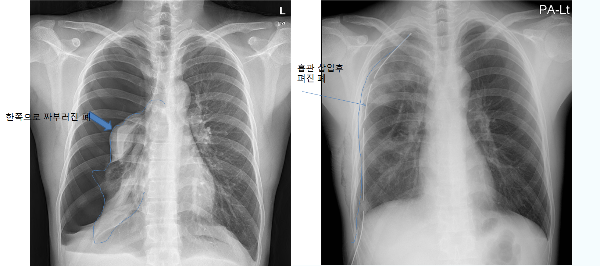

기흉 진단

신속한 진단이 중요합니다. 의사는 기흉을 확인하기 위해 다음과 같은 다양한 방법을 사용합니다:

흉부 엑스레이: 흉강 내 공기를 감지하는 가장 일반적인 방법입니다.

흉관 삽입: 더 심한 경우에는 흉관을 삽입하여 흉강 내 공기를 빼냅니다.